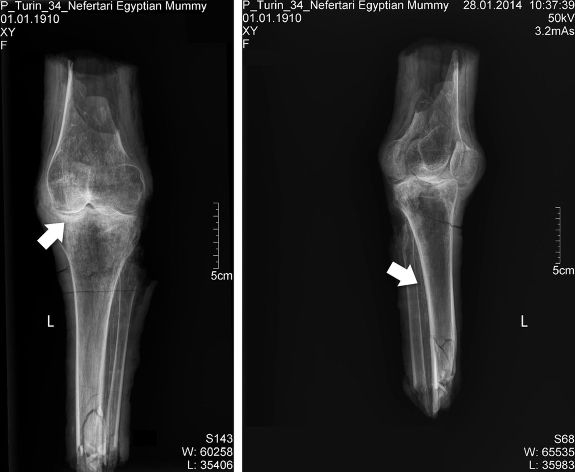

Фрагменты ног, найденные в гробнице Нефертари. Credit: Habicht et al., PLOS ONE 11(11): e0166571

Рентгеновские снимки ног Нефертари. На правом снимке стрелкой указаны следы кальциноза в артериях, на левом стрелкой указаны следы артрита. Credit: Habicht et al., PLOS ONE 11(11): e0166571

Рентгеновские лучи выявили признаки кальцификации на артериях, располагающихся вдоль большеберцовой кости, что, возможно, является признаком атеросклероза или других заболеваний, связанных с возрастными изменениями эластичности сосудов. Анализ ДНК провести не удалось из-за деградации и контаминации биологического материала. Биохимический анализ показал, что вещества, использовавшиеся при бальзамировании, в том числе обильное смачивание бинтов в животном жире, характерны для эпохи XIX-ХХ династий.